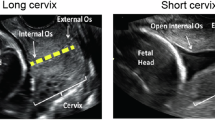

Similarly to our previous preliminary study15, one image of the uterine cervix was obtained for each woman. Images were acquired by experienced sonographers performing routine screening ultrasound. A sagittal view of the cervix was obtained. The internal and external os, as well as the cervical canal, were identified and the entire cervical structure visualized, avoiding zooming and using only the depth function. Shadows and saturations were avoided as possible. Any post-processing functions, such as speckle reduction imaging or smoothing, were disabled. Cervical length was measured online by the sonographer performing the examination and saved together with baseline demographic and perinatal outcomes. Gain was at the discretion of the physician. Images were acquired with Siemens Sonoline Antares (Siemens Medical Systems, Malvern, PA, USA) or VolusonE6 (GE Medical Systems, Zipf, Austria) ultrasound machines, with a 2–10-MHz vaginal probe by different operators. All study images were stored in the original Digital Imaging and Communication in Medicine (DICOM) format for further analysis.

DICOM images were processed using the novel automated quantitative test, called QUANTUSPREMATURITY and available online (www.quantusprematurity.org). The tool is very simple to use as it only requires the image to be uploaded online. Then, the test automatically delineates a region of interest (ROI) containing the entire cervix, see Fig. 1 and calculates a sPTB probability risk score, which is returned to the user in the form of a Portable Document Format (PDF) clinical report. This report contains the prematurity risk score estimated by the test, which was stored for further analysis.